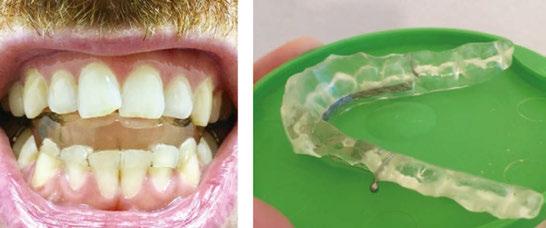

An OMD assessment with TMD muscle pain: a case study

Judith Dember-Paige, BSOHP, COM®, discusses how transformation sometimes takes years, but it’s worth the effort

Stan was referred to my office by a TMD specialist. His chief complaints were he could not chew or open his mouth without pain. It seemed the less he chewed, the more pain he experienced. As a result, an Orofacial Myofunctional Therapy (OMT) program was created to help support his muscles of the TMJ and craniofacial respiratory complex. He used his splint as instructed by his specialist. However, his anterior open bite widened, and his teeth became more misaligned over time.

Upon closer examination, there were contributing factors that led to his discomfort. Stan had been a stomach/face sleeper for years. He also bit his nails since childhood, had a smoking habit from his youth, and he was prone to ear infections. He had moderate tongue and buccal ties, obligate mouth breathing, aggravated by a deviated septum, narrow nares, low tongue resting posture, an anterior open bite, a lower jaw that deviated upon opening, and bouts of acid reflux.

When the tongue rests in the palate, it impacts facial development especially for children who are still growing. An adult, for example, like our friend Stan, the progress made is gradual but more likely to last a lifetime. Generally, therapy starts out once a week for about 2-3 months. Then therapy progresses to every other week for 2-3 months, and then changes to once a month for about 5 months for the rest of the year. The exercises are done a minimum of 2 times everyday. These exercises are designed to strengthen and tone the orofacial muscles, building brand new neuromuscular function. When the muscles of the face are well developed, it may favorably impact appearance and the overall integrity of the facial structures. The muscles of the face also include the tongue, lips, cheeks and neck. Although the therapy program is typically only a year, Stan really liked how good he felt and decided to continue with some of the exercises to this day. From the photos you can see how much the program has impacted his health and well-being.

During his therapy, there was a discussion about the possible benefits he may receive from having his jaws expanded, making more room for his tongue, then to be followed by a tongue and buccal frenums release. His intermolar width is 34 mm, and his intercanine width is 25 mm. I feel any expansion has a potential benefit.

To document any initial assessment, the midpoint of therapy, and when therapy has ended, it is important to take detailed photos, videos, plus full measurements of the face and teeth. This makes it possible to compare results while showing that your therapy works based on the evidence you gathered before, during, and after treatment.

Figure 5

Figure 6: No room for his tongue

Figure 4: 7 years later on April 10, 2024. Anterior open bite closed a bit

Figure 2: Initial assessment on December 15, 2016 (top left). Later September 20, 2017, his anterior openbite widened (top right)

Figure 3: Milled orthotic splint